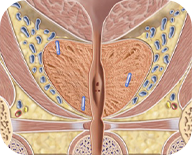

Fiducial marker insertion